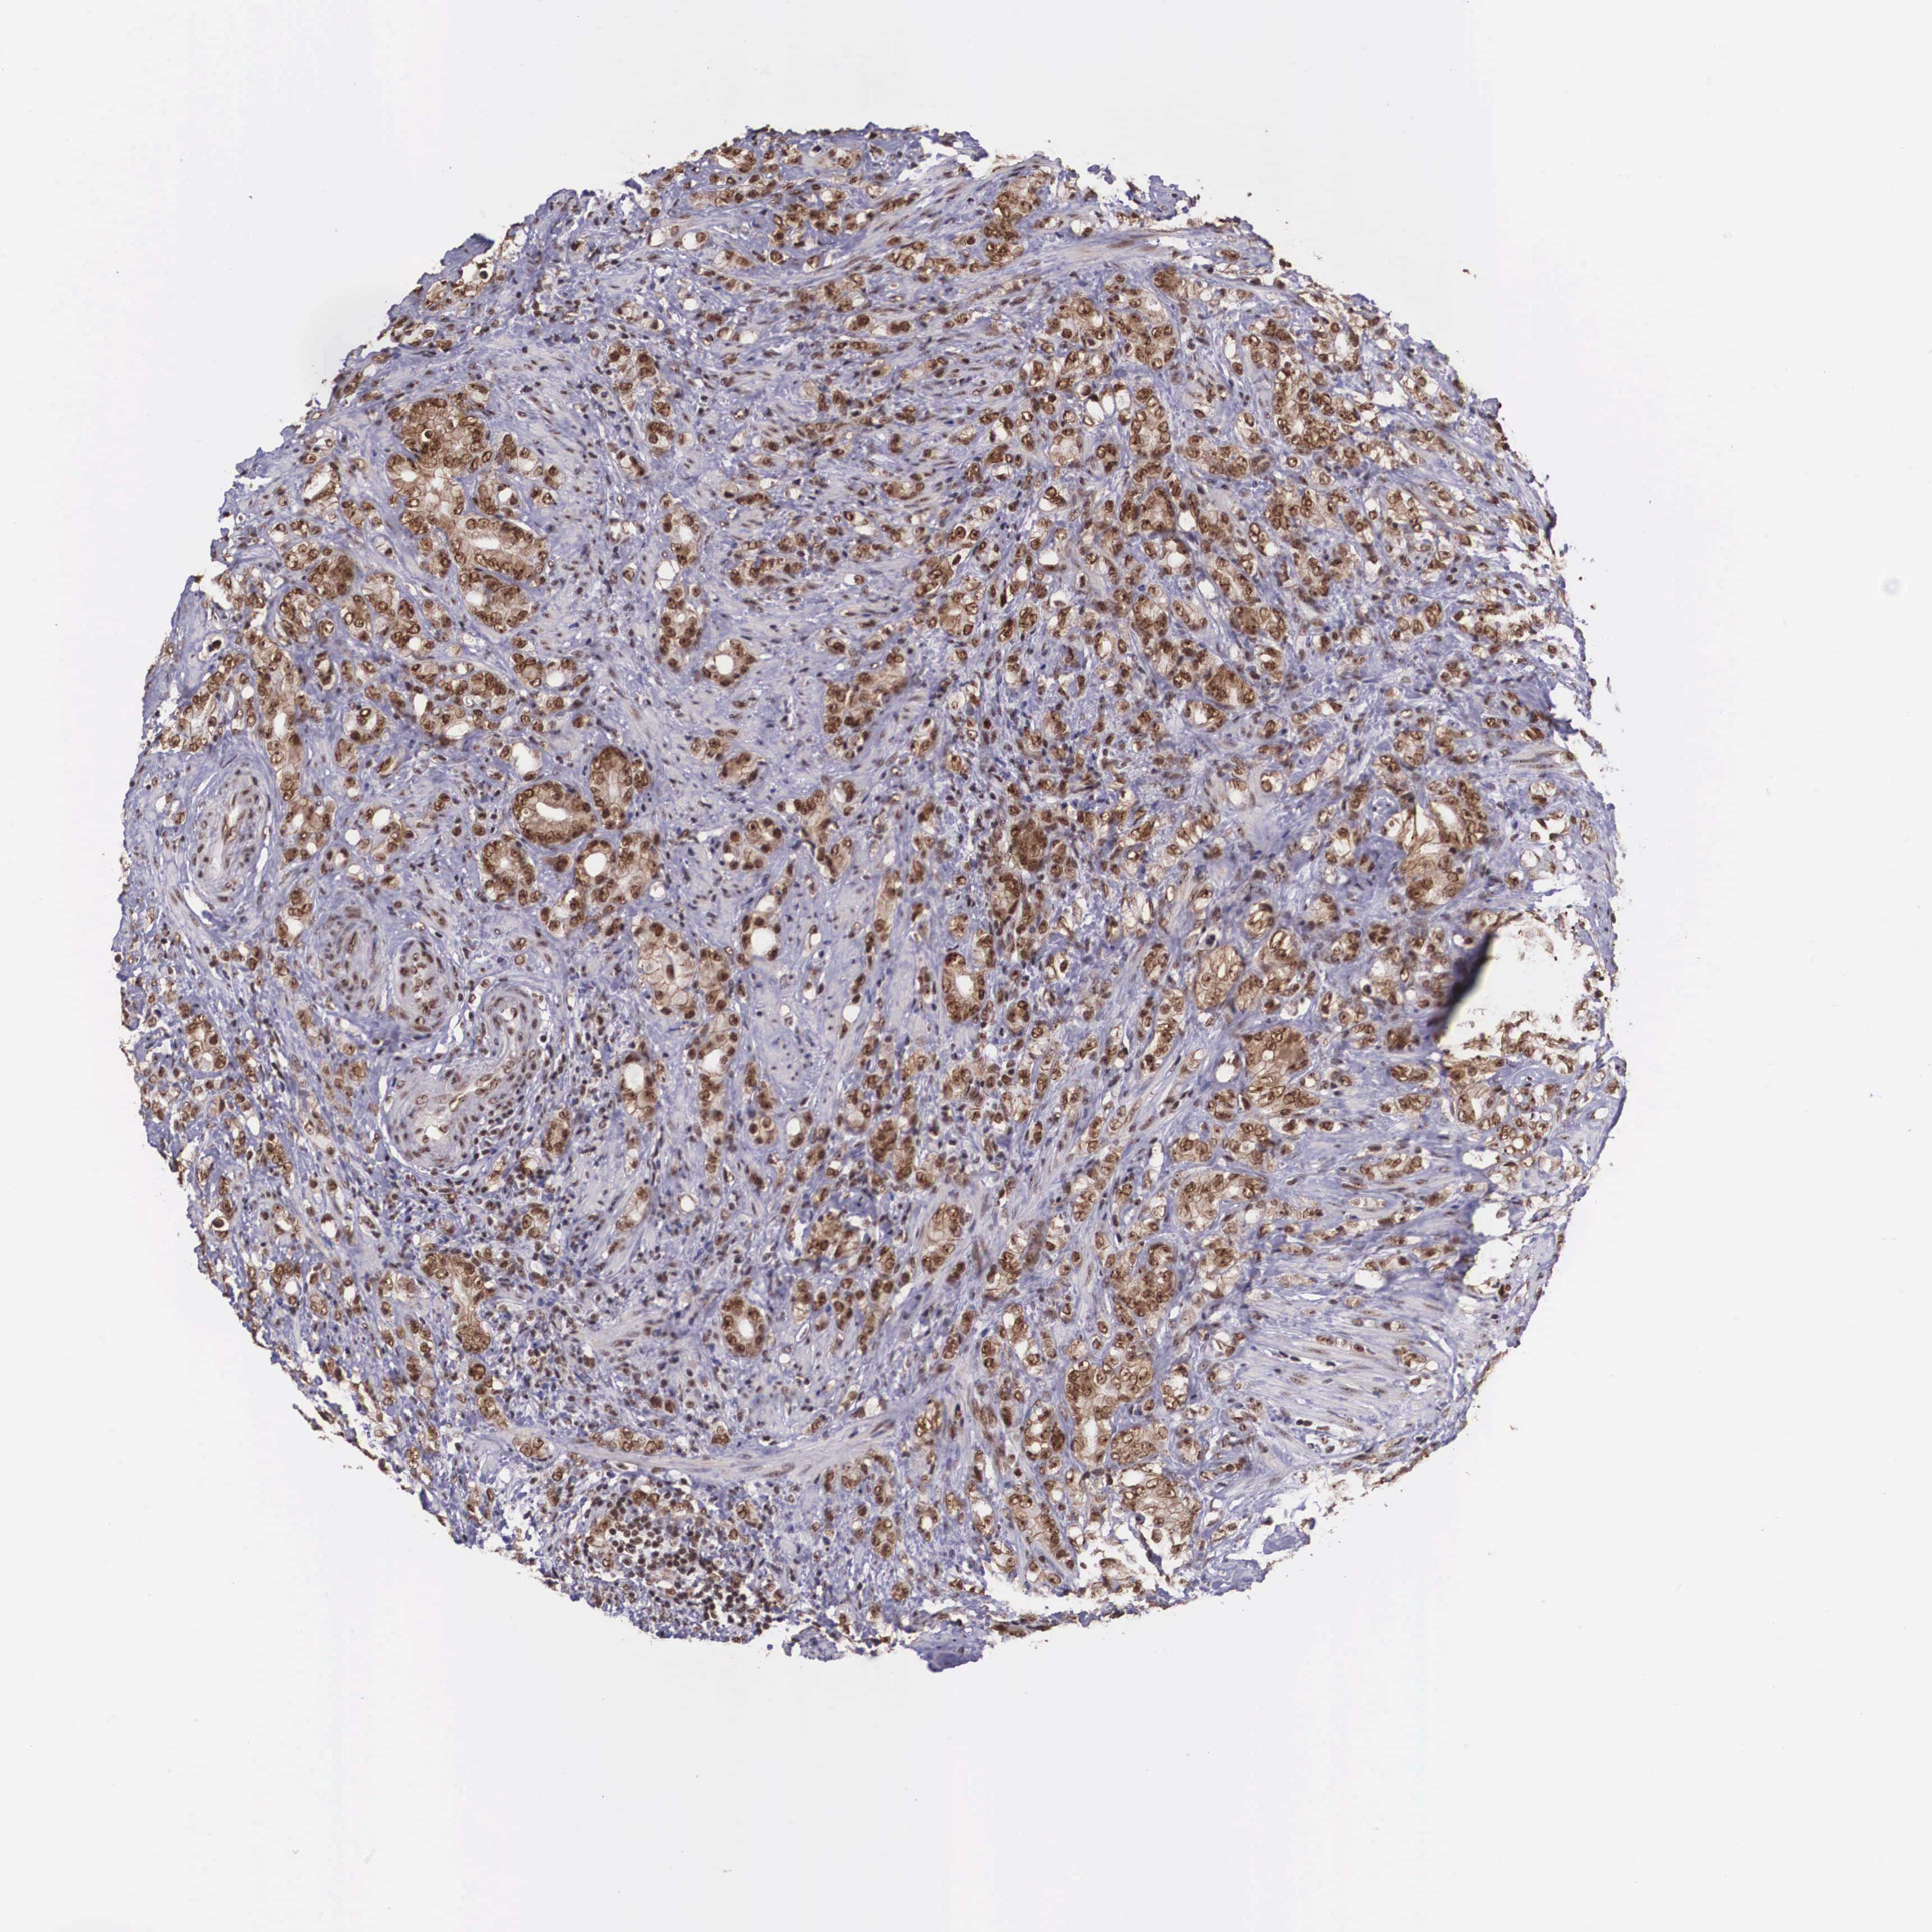

PROSTATE CANCER - Protein expressioni

A mouse-over function shows sample information and annotation data. Click on an image to view it in a full screen mode. Samples can be filtered based on level of antibody staining by selecting one or several of the following categories: high, medium, low and not detected. The assay and annotation is described here.

Antibody stainingi

Antibody staining in the annotated cell types in the current human tissue is reported as not detected, low, medium, or high, based on conventional immunohistochemistry profiling in selected tissues. This score is based on the combination of the staining intensity and fraction of stained cells.

Each image is clickable and will lead to virtual microscopy that enables deeper exploration of all samples and also displays staining intensity scores, fraction scores and subcellular localization as well as patient and tissue information for each sample.

Antibody CAB009882

Staining

High

Medium

Low

Not detected

Intensity

Strong

Moderate

Weak

Negative

Quantity

>75%

75%-25%

<25%

None

Location

Nuclear

Cytoplasmic/membranous

Cytoplasmic/membranous,nuclear

Adenocarcinoma, High grade